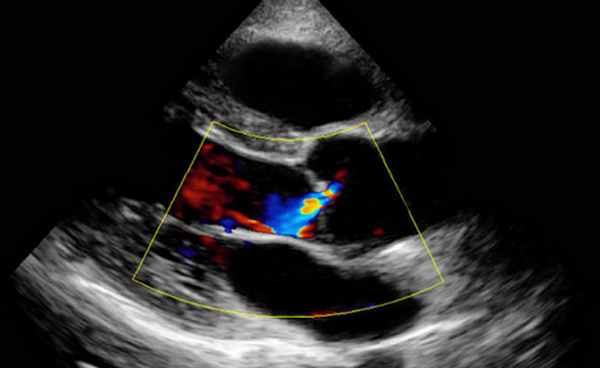

- ЭхоКГ. ЭХОКГ позволяет определить: структуру клапана (двустворчатый клапан, утолщение створок, фиброз, кальциноз, вегетации), характер его движения (подвижность створок, степень открытия) и площадь отверстия; изменения корня аорты (постстенотическая дилатация), объем левого желудочка, выраженность гипертрофии левого желудочка, нарушения локальной сократимости левого желудочка (указывающие на ИБС), ФВ, объем левого предсердия, состояние других клапанов. Доплеровское исследование позволяет с высокой точностью определить градиент давления между аортой и левым желудочком.

Митральная регургитация

• Vena contracta ≥7 мм.

• Эффективная площадь отверстия регургитации EROA ≥40 мм².

• Объем регургитации ≥60 мл.

• Фракция регургитации ≥50%.